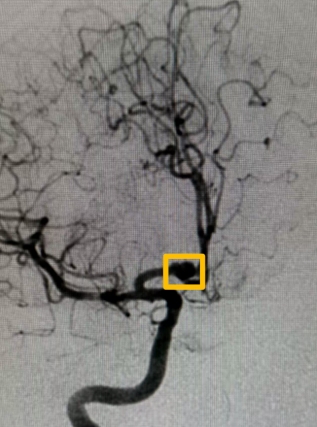

(▲术前)

李先生头颅CTA检查揭示了结果:前交通动脉瘤。突如其来的结果让患者和家属陷入了担忧之中。